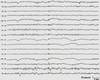

What stage of sleep is this found in?

Sleep Spindles

Define stage 2 sleep, ~13-14 Hz, max ~central

After 2 years of age, asynchronous sleep spindles are considered abnormal.